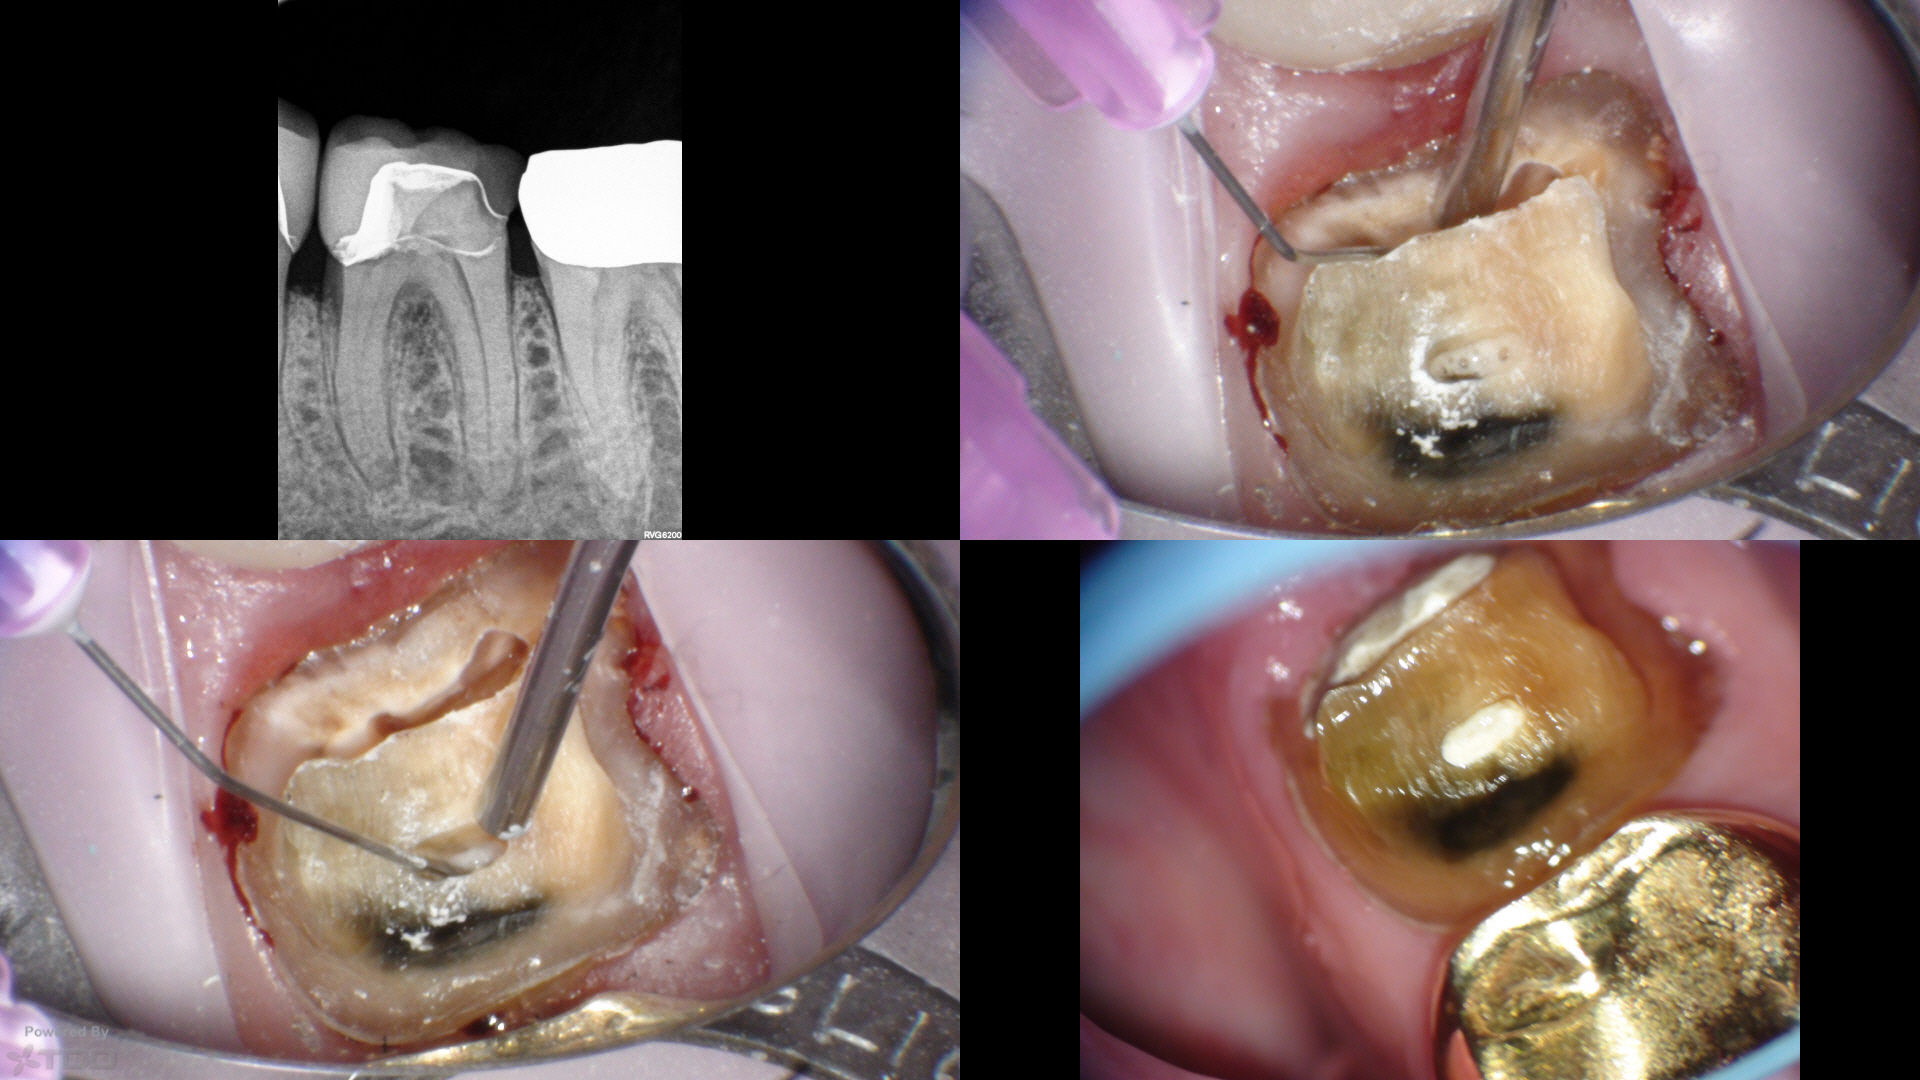

Here, traditional access would have removed most of the remaining PCD. We leveraged the caries and existing loss of tooth structure at the mesial, and poked a hole in the distal with an EG4. Chairside in the scope manages the field and NaOCl irrigation easily.

Temporary was left off with hygiene instructions. Tissue was healing well at 1wk, and was perfect today at 1mo complete (not shown). CBCT at the start visit suggested a missed DB, which was addressed at the complete visit today.

Resin mesial and distal.

Very nice! So what is the best restoration than manages the mesial margin, since its at the soft tissue margin? A feather edge on tooth or restorative material?

With a skilled restorative dentist and technician a feather edge gold restoration is do-able…but I’m talking beyond my pay grade.

Here, the VertiPrep would probably be best as tooth structure is available 360. This will probably get a light chamfer and gold however…